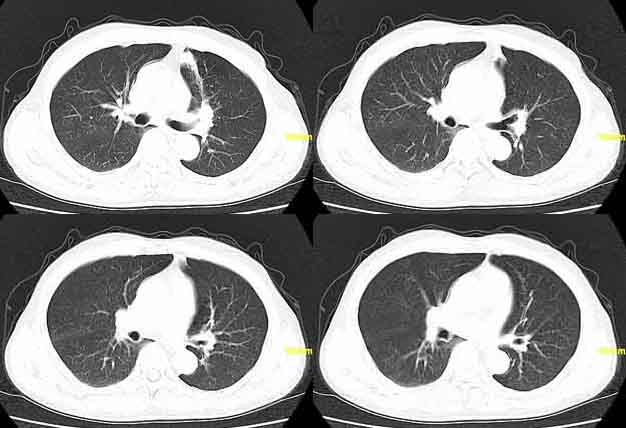

患者,男,76,反复咳血,余病史不详。

左肺上叶相当于前段可见条片状模糊影,,部分呈结节状实变,相应肺门好象显示尚可,上叶支气管阻塞不明显.考虑结核,建议治疗后复查或纤支镜检查

左肺舌叶上舌段见片絮状密度增高影及索条影,索条影与前壁胸膜相连,考虑炎症所致,建议抗炎治疗后复查。

要考虑阻塞性肺炎,第二幅肺部图象舌叶似乎有阻塞性肺气肿,建议一月后复查

左肺上叶前段片絮状模糊影,考虑感染性病变,以炎性改变可能性大,建议抗炎后复查或进一步结合实验室检查,毕竟病人有咯血史,应引起重视。

左肺舌叶上舌段见片絮状密度增高影及索条影,索条影与前壁胸膜相连,考虑炎症所致,建议抗炎治疗后复查